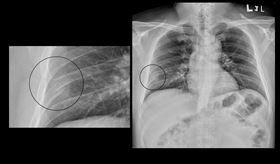

高瘦男胸痛以為火燒心!醫照X光:氣胸了

許多人有胃食道逆流的困擾,還可能引發胸悶問題。肝膽腸...

胸痛勿輕忽! 圖解氣胸5大成因一次搞懂

台中27歲簡先生身材高瘦,擁有總讓旁人羨煞吃不胖的體...